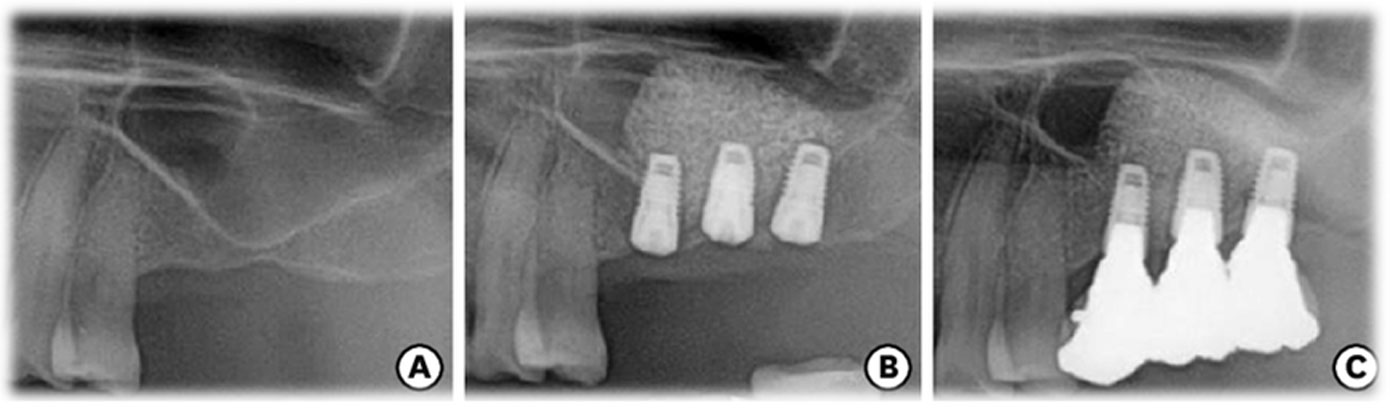

Guided Implant Surgery involves the use of advanced 3D imaging and computer-aided design (CAD) to plan the exact placement of dental implants. This meticulous planning process allows our dental specialists to visualize the patient’s oral anatomy in great detail, ensuring the implants are placed in the most ideal position for both functionality and aesthetics. The procedure is tailored to each patient's unique needs, ensuring a personalized treatment plan.

These technique assures that the implant is precisely placed without any damage to nerves, vessels and wouldn't perforate maxillary sinus too.